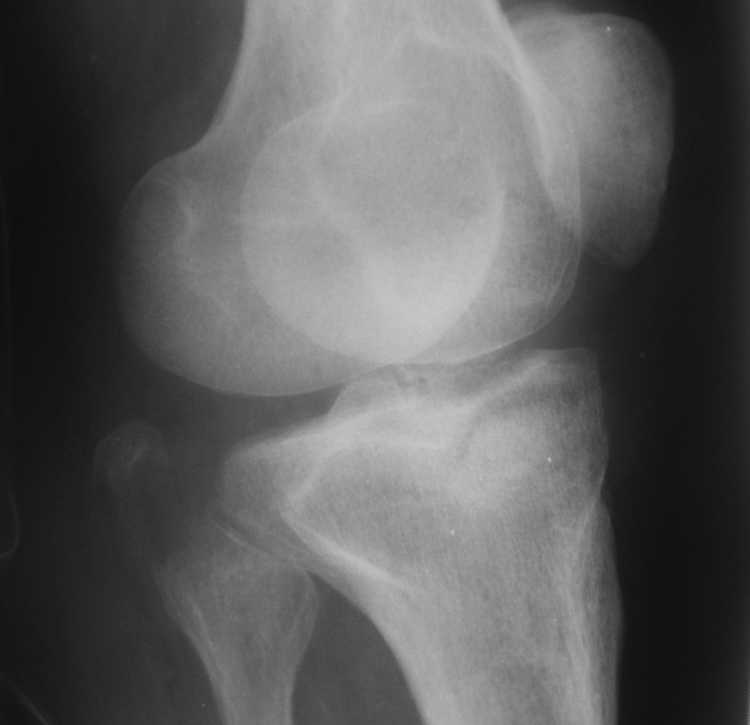

Re: Помогите определиться - перелом мыщелков правой большеберцовой кости

Высылаю рентгенограммы